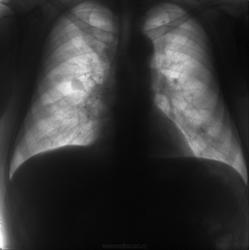

Флюорограммы в динамике. Последние две - прямая и боковая в 2012 г.

Флюорограммы в динамике.

11.21.09.2009.jpg12.1.10.2010_-1.jpg13.1.10.2010.jpg14.14.02.2012_-1.jpg15.14.02.2012.jpg

Согласен, наиболее вероятно метастазирование. В 2010 на боковушке, чуть ниже корня уже виден метастаз.